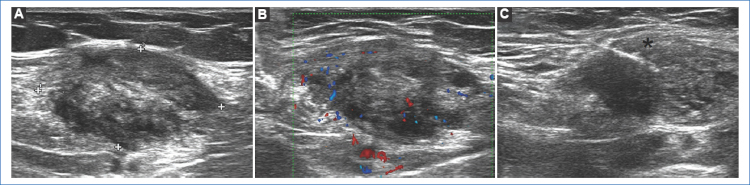

La punción-biopsia bajo ecografía es un método accesible y mínimamente invasivo para el diagnóstico de endometriosis de cicatriz. El hallazgo de tejido glandular endometrial, células estromales y macrófagos cargados con hemosiderina confirma el diagnóstico de endometriosis6-8.

Presentamos el caso de una paciente de 37 años, con antecedentes de cesárea (G1P0C1) dos años atrás, que consulta por una masa palpable no móvil en la pared abdominal anterior, en situación parasagital izquierda, en relación a una cicatriz de cesárea, de un año de evolución. La masa presentaba pequeño tamaño y se asociaba a dolor cíclico que aumentaba durante la menstruación, disminuyendo en los días intermenstruales. No se revelaron otros antecedentes de importancia al momento de la consulta. El médico derivante ordenó una TC abdominopélvica con contraste oral y endovenoso, que demostró la presencia de una imagen nodular con realce luego de la administración de contraste endovenoso en el espesor del músculo recto anterior izquierdo del abdomen, sin compromiso de la cavidad abdominal (Fig. 1). Debido a los hallazgos evidenciados y los antecedentes ginecológicos (cesárea previa y aumento del dolor en el ciclo menstrual), la probabilidad era muy alta para enfermedad endometrial, por lo que se descartó proseguir con otros estudios imagenológicos10 y se solicitó una punción-biopsia guiada por ecografía (Fig. 2). Este procedimiento se llevó a cabo utilizando un transductor lineal de 7.5 MHz (ecógrafo Esaote MyLab Twice) y una aguja Franseen de 20 G. La biopsia, mediante estudio citológico e histológico, confirmó el diagnóstico de endometriosis (Fig. 3).